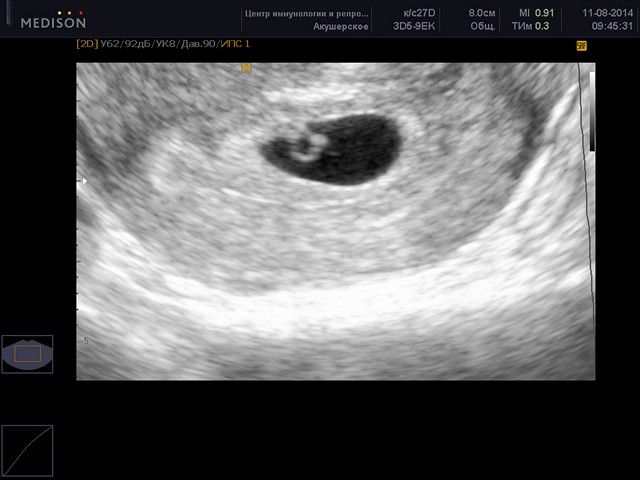

Основным способом диагностики является ультразвук через брюшную стенку или вагинально. На ранних сроках иногда можно перепутать полип с беременностью. Хотя некоторые специалисты отрицают такую возможность, фактов на женских форумах встречается достаточно. Грамотный узиолог не только установит наличие образования, но и детально опишет структуру, размеры, локализацию, предположит тип.